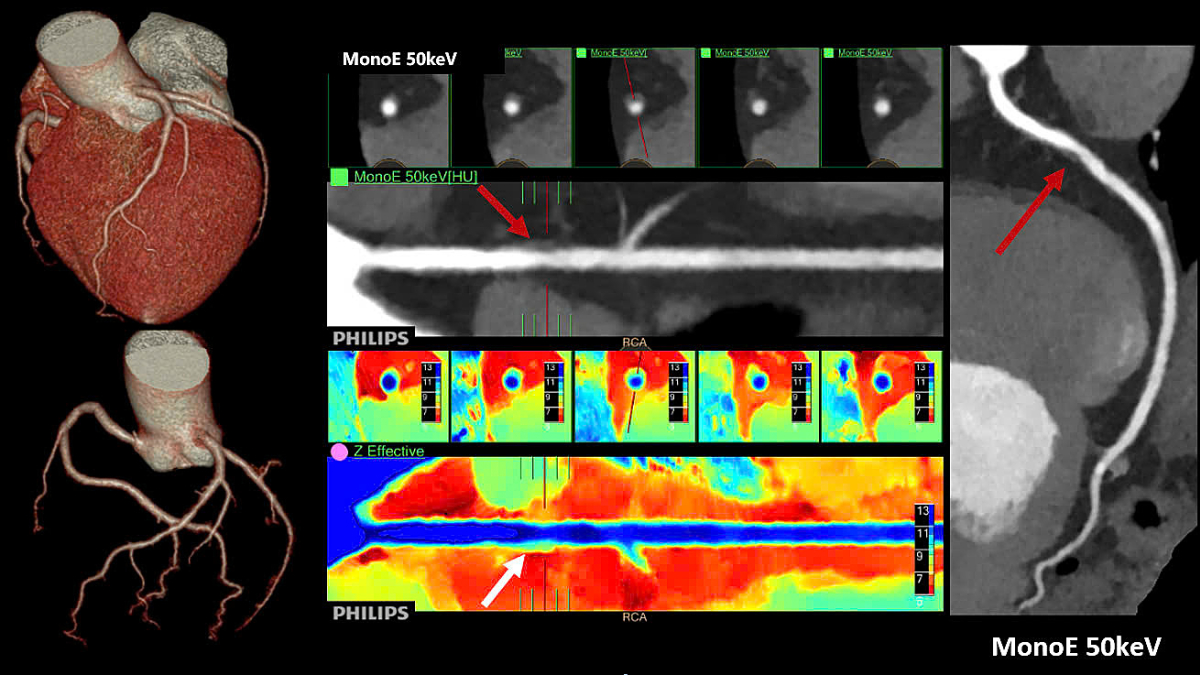

Nâng cao khả năng chẩn đoán bệnh

Một nghiên cứu tại Đức với sự tham gia của gần 500.000 phụ nữ đã chỉ ra rằng việc tích hợp AI trong sàng lọc ung thư vú giúp phát hiện thêm một ca bệnh trên mỗi 1.000 người được kiểm tra. Việc sử dụng AI để phân tích hình ảnh nhũ ảnh giúp bác sĩ chẩn đoán chính xác hơn, đồng thời không làm tăng nguy cơ tổn thương hay sai lệch kết quả đối với bệnh nhân.

Giáo sư Alexander Katalinic, đồng tác giả nghiên cứu, cho biết phương pháp này vừa tăng hiệu quả phát hiện bệnh, vừa giảm áp lực cho bác sĩ X-quang.